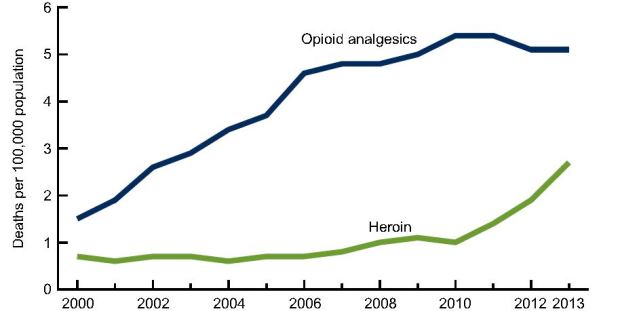

An NSC poll found this to be true even though sharing narcotic opioid painkillers is the equivalent to selling heroin in most states.

The age-adjusted rate for drug overdose deaths involving heroin jumped from 0.7 deaths per 100,000 in 2000 to 2.7 deaths per 100,000 in 2013, according to a new CDC report, and most of the increase occurred after 2010.